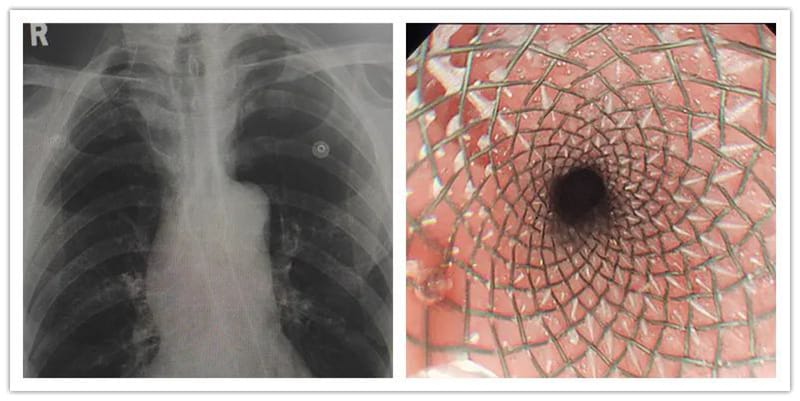

病例一:老年患者王某某,确诊食管癌3+月,外院化疗术后2月后就诊。该患从发现时食管腔已是重度狭窄,经化疗后,虽癌肿缩小,但因瘢痕形成,狭窄更甚,从最初的流质饮食,到如今的稀饭都无法下咽,患者异常痛苦,骨瘦如柴。入院完善相关检查后,在郭军主任的指导下,消化内科贺黔黔医生成功为其实施了内镜下食管癌支架置入术,术后患者无任何不适,第二天已可进流质饮食。此时正逢端午佳节,老人已能少量进食,对于一个长期不能进食的患者来说,手术的成功为提高患者后期生活质量意义非凡,后期消化内科将在临床营养科的指导下,继续给予患者营养支持治疗。

食管癌化疗前(左)及支架置入前(右)

支架置入后